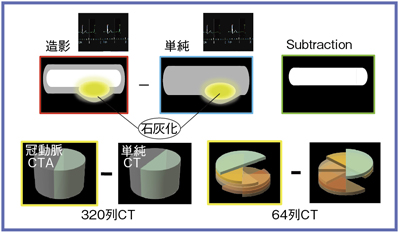

Amazon.com: CT冠動脈造影実践学: 9784498013568: unknown, 冠動脈CTによる狭心症の診断,

冠動脈CTによる狭心症の診断, 沖縄県医師会_沖縄県医師会報(2013年3月号),

沖縄県医師会_沖縄県医師会報(2013年3月号), 放射線 CT - 榊原記念病院,

CT装置|徳島赤十字病院, 320列面検出器CTによる新しい冠動脈CT技術 吉岡邦浩(岩手医科,